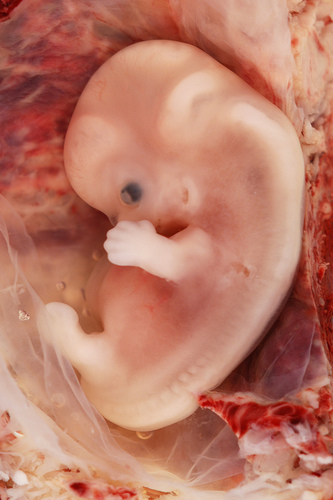

amazed that at 11 weeks, who my grandchild is, has already been determined…

heart, arms, organs, legs, ears, eyes, fingers, toes are forming and growing.

from the looks of that emryo picture it looks like hes going to take after his dad and have a ridiculously huge head. Poor thing! HAHAHA Poor Amber